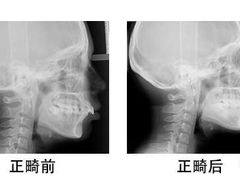

• 浙江大学医学院附属口腔医院湖滨(延安)院区